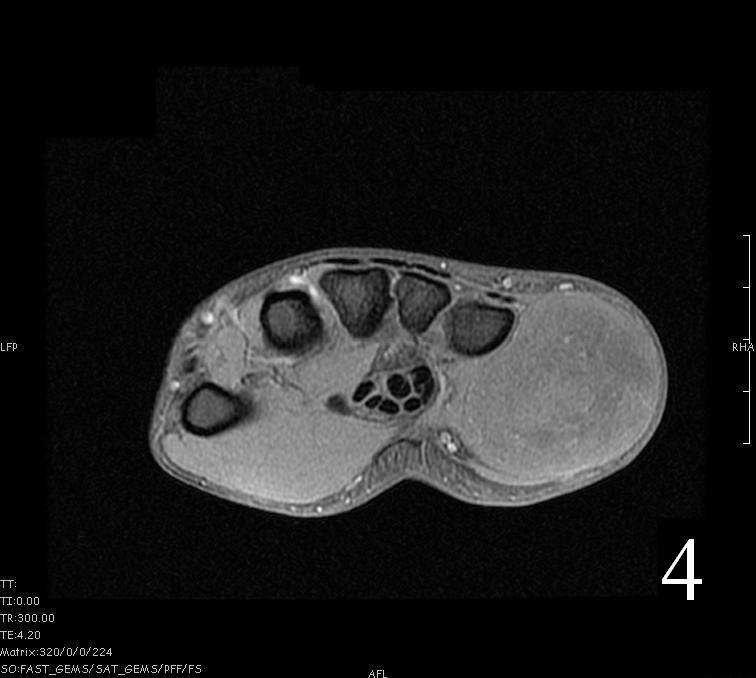

MRI

- Heterogeneous mass (does not follow signal of skeletal muscle)

- Isointense to skeletal muscle on T1 (Fig. 4, Fig. 5, Fig. 7, Fig. 8)

Fig. 4-9: MRI of a rhabdomyosarcoma of the hand. The MRI is nonspecific and shows a heterogeneous mass particularly on postgadolinium images T1 W images (Fig. 8) and T2 W images (Fig. 9).